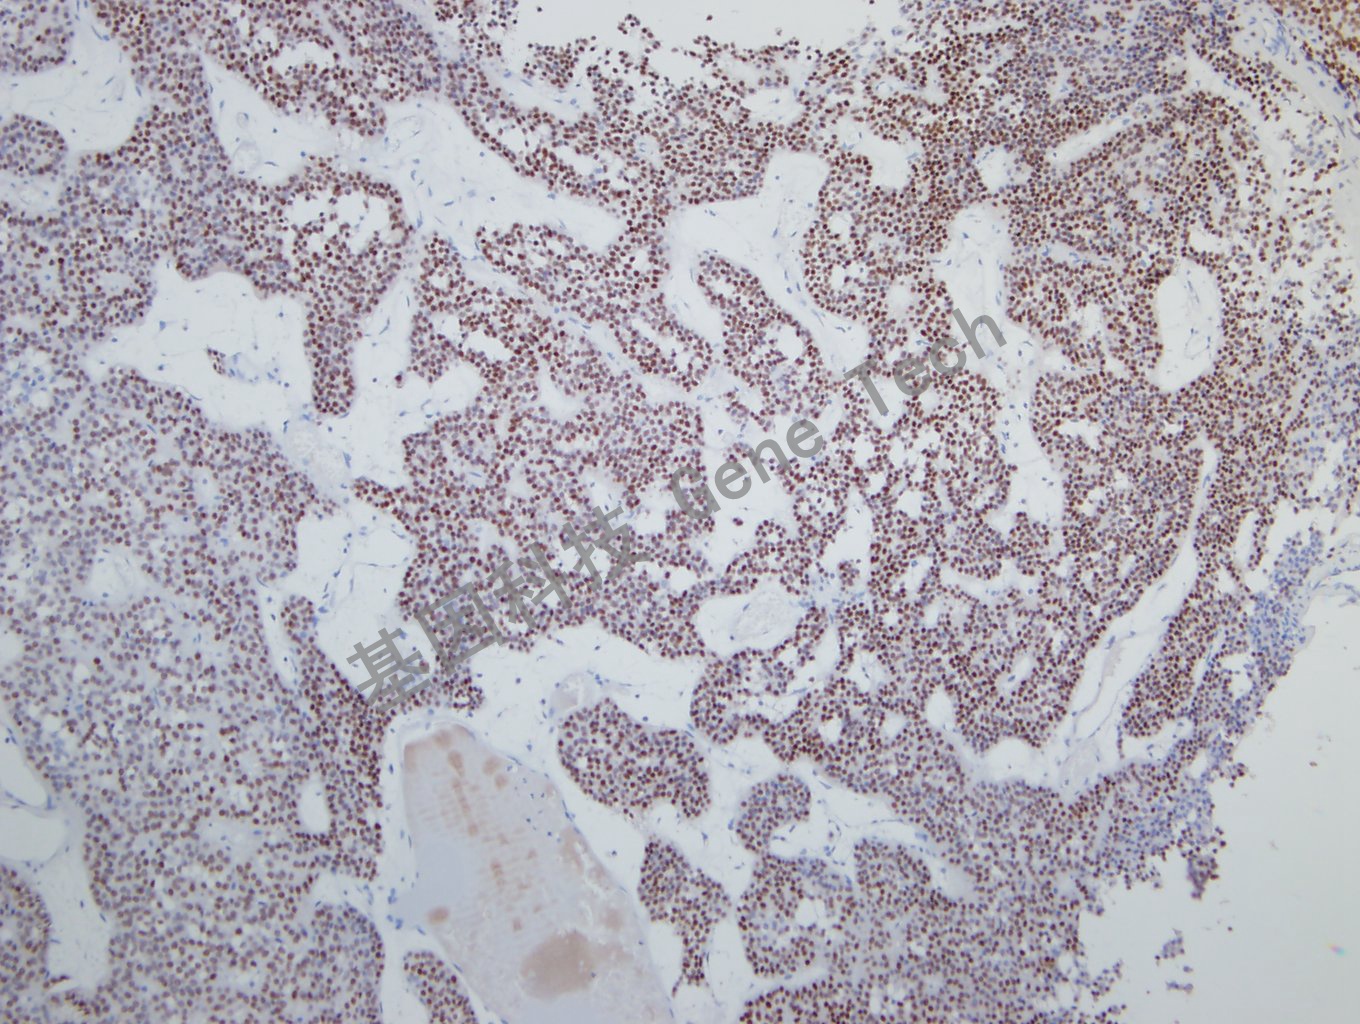

垂体腺瘤石蜡切片,用 SF-1(GT2317)染色,细胞核阳性,DAB显色。